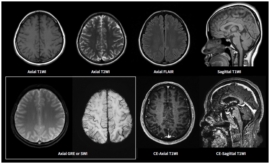

MRA와 MRI는 모두 자기 공명 현상을 이용하여 인체의 내부 구조를 촬영하는 비침습적인 의료 영상 기술입니다. 하지만 이 두 가지는 그 촬영 목적과 방법에서 큰 차이를 보입니다. 먼저, MRI는 인체의 다양한 조직을 상세하게 시각화하는 데 초점을 맞추고 있습니다. 이는 주로 뇌, 척수, 관절, 그리고 복부 장기 등을 평가하는데 사용됩니다. MRI는 강력한 자석과 전자기파를 이용해 인체 내부의 수소 원자의 반응을 기록하여 이미지를 생성합니다. 이는 고해상도의 이미지를 제공하여 전문가들이 각종 질병이나 이상을 진단하는 데 매우 유용합니다.

MRI는 인체 내부의 조직을 정밀하게 진단하기 위해 설계된 의료 영상 기술입니다. MRI의 가장 두드러진 특징은 다양한 조직의 차별적 이미징이 가능하다는 점입니다. 예를 들어: 신경 조직, 근육, 뼈, 지방 등 다양한 조직을 일정 수준 이상으로 구별하여 보여주는 것이 가능합니다. 이로써 MRI는 다양한 질병의 조기 진단 및 치료 경과 모니터링에 큰 도움이 됩니다.

- 뇌질환 평가: MRI는 뇌 tumors, 신경계 질환 및 인지 장애를 평가하는 데 최고의 진단 도구로 자리잡았습니다.

MRI의 장점은 무엇보다도 높은 해상도의 이미지를 제공한다는 것입니다. 이는 병변을 보다 명확하게 규명하는 데 도움을 주며, 치료 결정의 정확성을 높일 수 있습니다. 뿐만 아니라, MRI는 방사선 비노출이라는 특징 덕분에 건강 위험이 적고, 안전한 검사법으로 폭넓게 활용되고 있습니다.